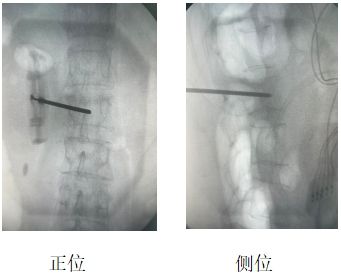

患者辛某(化名),女性,69歲,因“腰部劇烈疼痛伴活動(dòng)受限2天”入院。既往有骨質(zhì)疏松癥病史,影像學(xué)檢查提示L2椎體新鮮壓縮性骨折,VAS評(píng)分8分。

當(dāng)?shù)蒯t(yī)院建議外科手術(shù)治療,患者及家屬拒絕開(kāi)刀手術(shù),遂來(lái)我院疼痛科。結(jié)合患者自身情況,劉康主任與科室人員經(jīng)討論,決定行“經(jīng)皮椎體成形術(shù)(PVP)”聯(lián)合“脊神經(jīng)后內(nèi)側(cè)支射頻調(diào)控術(shù)”,同時(shí)解決椎體穩(wěn)定性與神經(jīng)源性疼痛問(wèn)題。